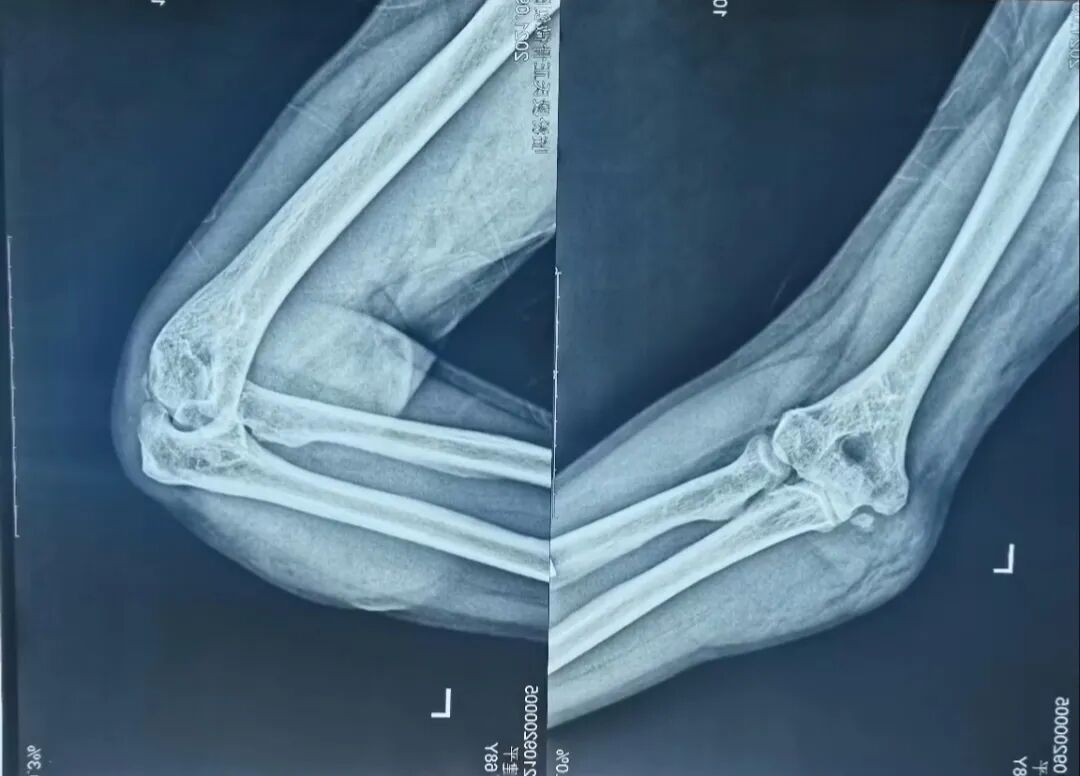

(肘关节大脱位)

(传统手法复位)